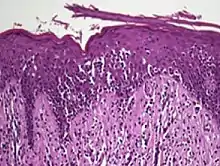

Histology

The criteria for the disease are established on the skin biopsy by the presence of the following:[18]

- Presence of cancer cells with twisted contours (cerebriform nuclei)

- In the patch and plaque stages, the cancer cells are seen in the epidermis (the most superficial layer of skin).[19] This is referred to as epidermotropism.

- Pautrier's microabcesses, aggregates of four or more atypical lymphocytes arranged in the epidermis. Pautrier microabcesses are characteristic of mycosis fungoides but are generally absent.

- In the tumour stage, the cancer cells move into the dermis (the deeper layer of skin)[19]

- Large cell transformation, where clonally identical lymphocytes in the lesion exhibit hypertrophy. In transformed cells, presence of the CD30 receptor is associated with improved survival[20]

To stage the disease, various tests may be ordered, to assess nodes, blood and internal organs, but most patients present with disease apparently confined to the skin, as patches (flat spots) and plaques (slightly raised or 'wrinkled' spots).

Traditionally, mycosis fungoides has been divided into three stages: premycotic, mycotic and tumorous. The premycotic stage clinically presents as an erythematous (red), itchy, scaly lesion. Microscopic appearance is non-diagnostic and represented by chronic nonspecific dermatosis associated with psoriasiform changes in epidermis.

In the mycotic stage, infiltrative plaques appear and biopsy shows a polymorphous inflammatory infiltrate in the dermis that contains small numbers of frankly atypical lymphoid cells. These cells may line up individually along the epidermal basal layer. The latter finding if unaccompanied by spongiosis is highly suggestive of mycosis fungoides. In the tumorous stage a dense infiltrate of medium-sized lymphocytes with cerebriform nuclei expands the dermis.